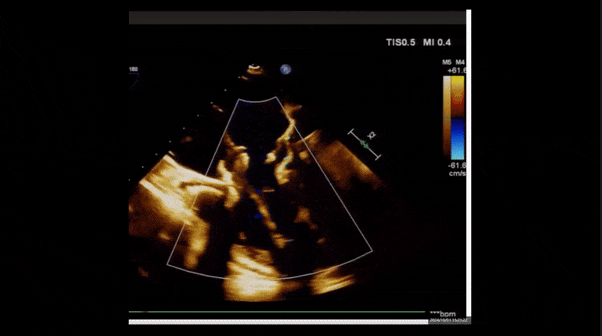

術(shù)后三維超聲

術(shù)后即刻經(jīng)食道超聲可見,三尖瓣假體瓣膜位置合適,牛心包瓣葉運(yùn)動狀態(tài)良好,開閉正常,瓣周及瓣葉對合緣處未見明顯返流,心電圖及心包狀態(tài)較術(shù)前無明顯變化。

術(shù)前術(shù)后返流情況對比